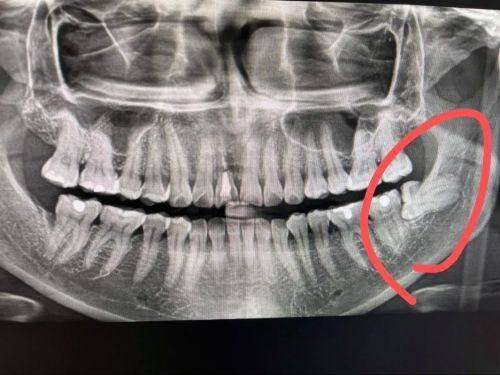

患者情况:28岁上班族,左下智齿完全埋伏在骨头里,CT显示牙冠顶着前牙牙根,牙根呈“C形弯根”,离下牙槽神经仅0.5毫米。

技术亮点:3D CT术前规划 + 超声骨刀去骨 + 分根拔除

过程揭秘:医生先通过CT重建牙齿3D模型,标记神经位置和去骨范围;然后用超声骨刀(振动频率精细到微米,只切骨头不损伤软组织)去除表面骨质,暴露牙冠;再用高速手机将牙冠劈开,根据牙根弯度分段取出,全程没碰到神经。术后肿胀轻微,3天修复正常饮食。

患者反馈:“以为要肿成猪头,结果就像轻微口腔溃疡,太神奇了!”